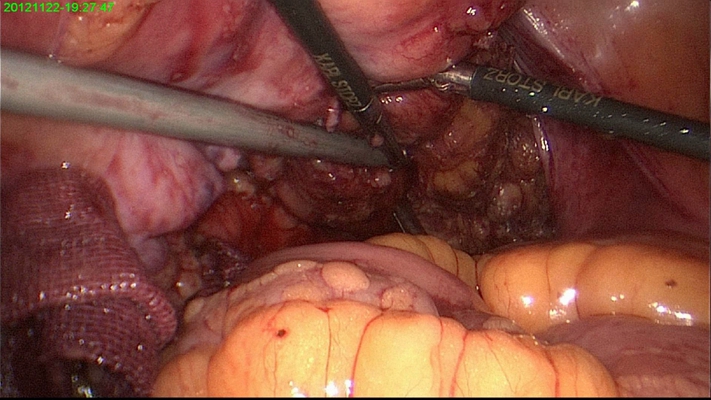

直腸癌圖片